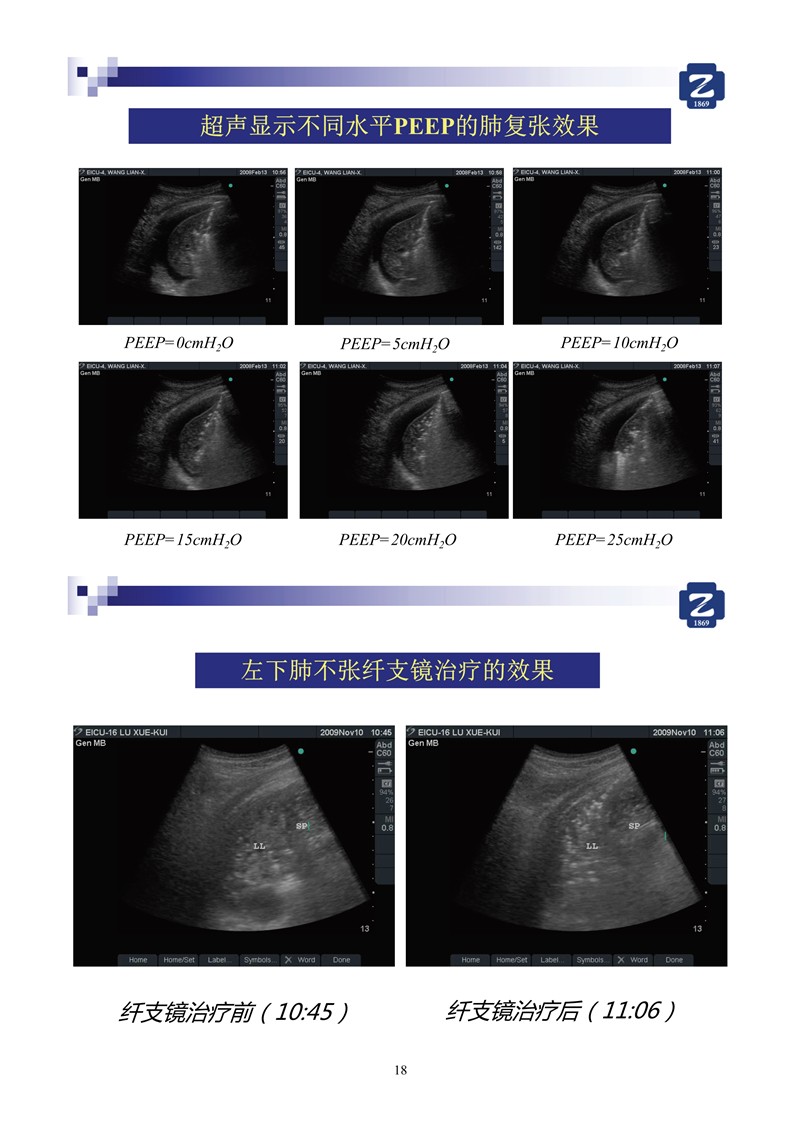

第二版新型冠狀病毒肺炎超聲診斷實(shí)用手冊(cè)_2.jpg